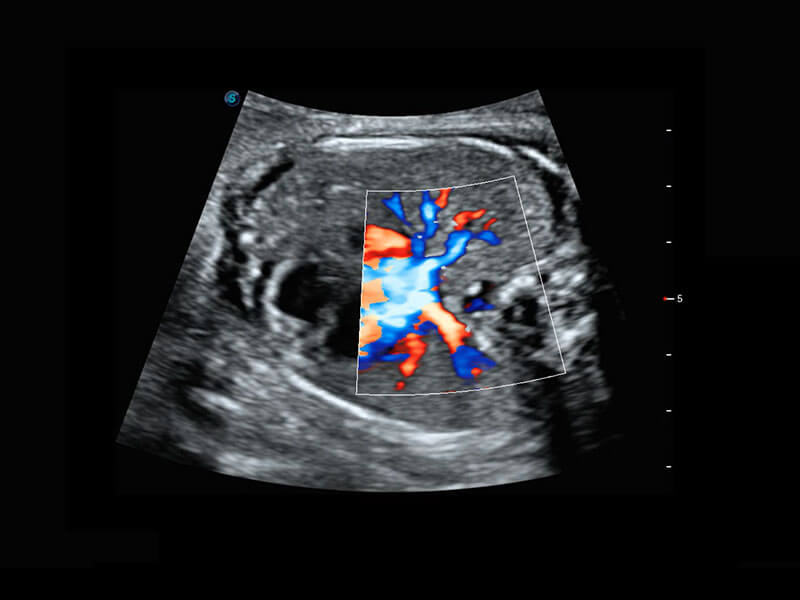

早孕-胎心

P60在胎儿早孕期超声筛查中为您带来优异的图像质量。